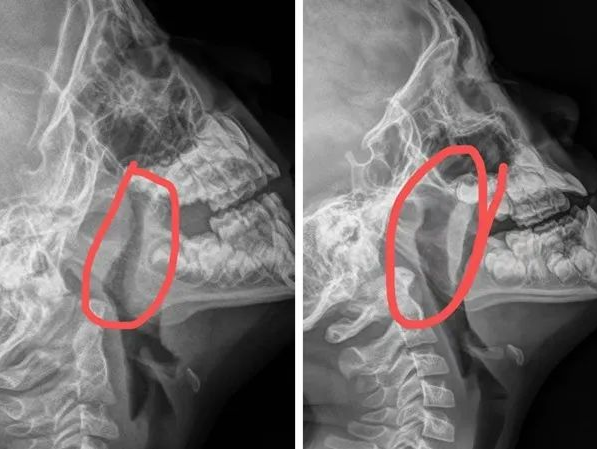

▶ 图例

通过以上两个X线片的对比,能明确看出,图左气道因腺样体肥大受限严重,供氧减少,长期则影响生长发育。